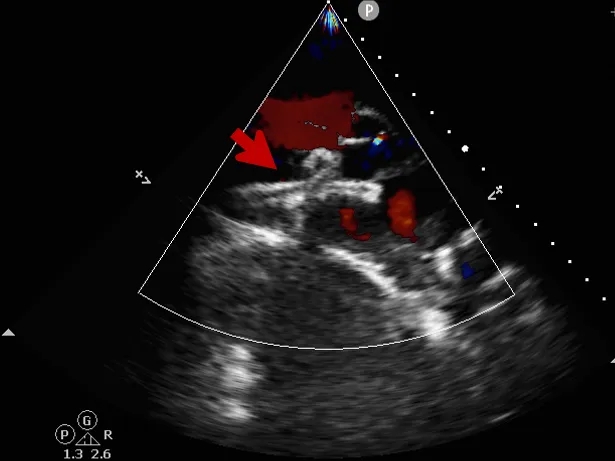

术中复测

超声可见房间隔连续中断,彩色多普勒可见过隔血流

测量房间隔缺损直径最大为23.9mm,房间隔总长53.8mm

心尖四腔心切面可见封堵器形态良好

主动脉短轴切面可见封堵器呈“Y”字型抱住主动脉

彩色多普勒血流成像显示无残余分流存在